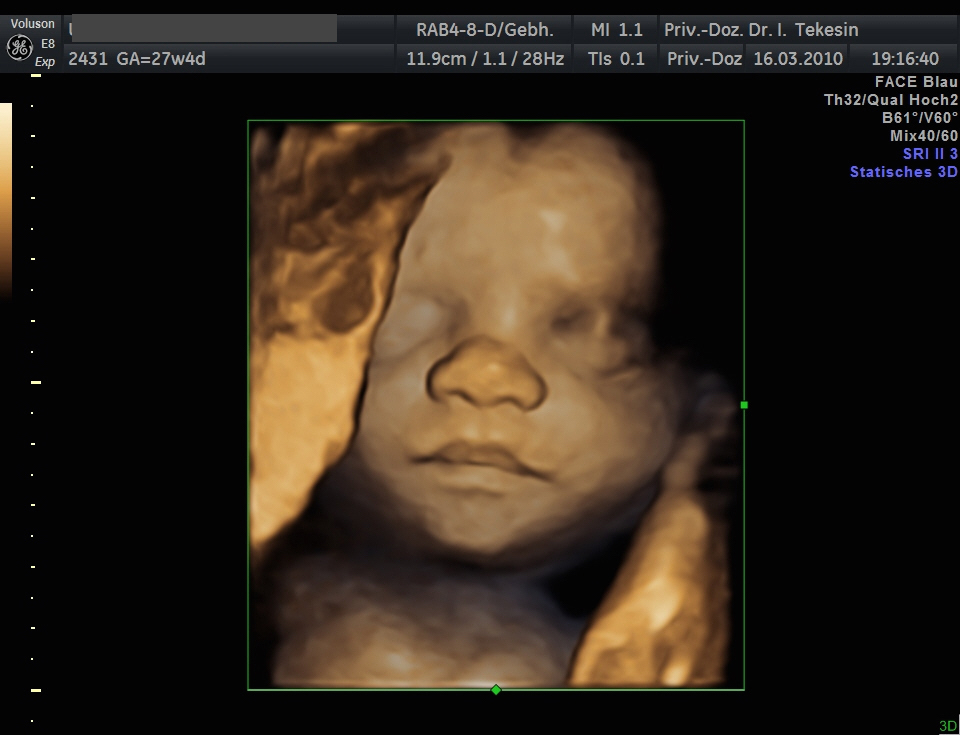

Kind in der 28. Woche (3D-Darstellung)